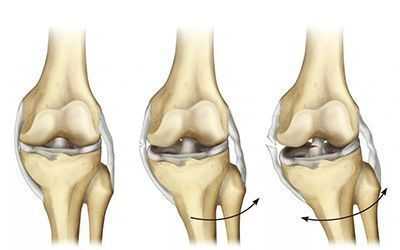

Определение болезни. Причины заболевания

Разрыв передней крестообразной связки (anterior cruciate ligament injury) — это одна из самых тяжёлых травм коленного сустава. Повреждение сопровождается щелчком в колене и невозможностью продолжать физическую активность. Затем появляется отёк и становится трудно сгибать и разгибать ногу в суставе.

Разрыв передней крестообразной связки (ПКС) является частой травмой коленного сустава. Встречается в 4 случаях на 1000 человек и занимает второе место после травмы мениска. ПКС — это самая травмируемая связка коленного сустава. Для сравнения: повреждения задней крестообразной связки встречаются в 15–30 раз реже, так как она примерно в 1,3–2 раза толще и в 2 раза прочнее ПКС [11] .

Прямая травма — возникает при ударе по бедру, голени и колену. Чаще встречается у спортсменов, например у футболистов, борцов и боксёров. Реже разрыв связки происходит при ДТП.

Непрямая травма — возникает, когда нет прямого удара по коленному суставу. Может произойти из-за резкого отклонения бедра с туловищем внутрь или наружу. Голень при этом повёрнута или фиксирована. Из-за такого отклонения в коленном суставе возникает «скручивание», вызывающее разрыв связки.

Чаще всего ПКС разрывается при отклонении голени наружу и кручении бедра внутрь. Особенно такая травма распространена среди спортсменов: футболистов, гандболистов, баскетболистов и волейболистов.

Зачастую при такой травме, помимо разрыва ПКС, повреждается внутренний мениск, а при сильном скручивании разрывается внутренняя боковая связка. Такое сочетание повреждений называют «несчастливой триадой» или «взрывом коленного сустава» [1] . При отклонении голени внутрь и кручении бедра наружу к травме ПКС может присоединиться разрыв наружного мениска.

Основная функция ПКС — удерживать голени от смещения. Чаще всего разрывы связки вызваны кручением на опорной ноге, когда бедро и корпус вращаются, а голень со стопой остаются фиксированными. Повреждение ПКС приводит к нестабильности в коленном суставе, т. е. дискомфорту от смещения голени относительно бедра.

Если такое состояние длится долго, то суставные хрящи, мениски и остальные структуры сустава изнашиваются и развивается деформирующий артроз. Этот процесс протекает с разной скоростью, зависящей как от травмирующего агента, так и от генетической предрасположенности. Со временем пациент начинает ощущать ноющую боль в колене, сначала при длительной нагрузке, а затем и в покое, дискомфорт не проходит даже во сне.

Больной начинает « щадить » ногу и меньше на неё опираться. Из-за этого нарушается биомеханика походки, увеличивается нагрузка на структуры сустава и возникает вальгусная (X-образная) либо варусная (O-образная) деформация.